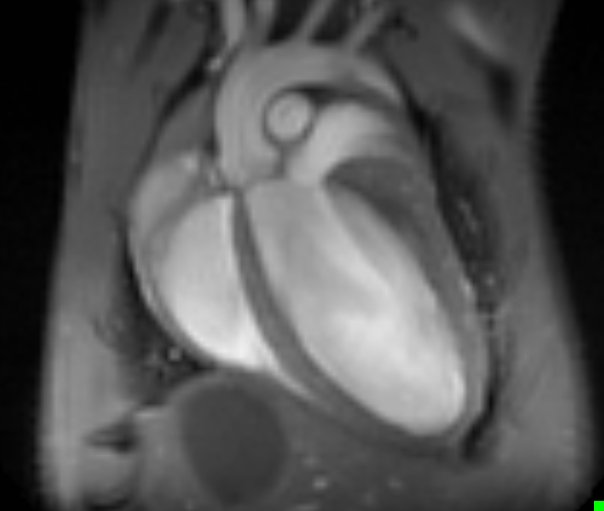

Komplexe Steuerungsprozesse für ein komplexes Organ: Wie zwei verwandte Proteine zusammenarbeiten um die Entwicklung des Herzens zu steuern.

RBPMS und RBPMS2 regulieren Zellteilung und -funktion während der Herzentwicklung